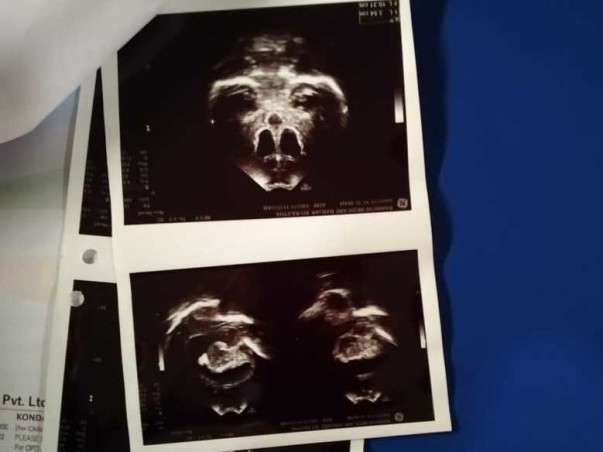

Bramarambika lives in Hyderabad, Telangana with us. The baby is suffering from brain TB Post-treatment for the past few months. The baby has undergone an operation we need support for post-surgery treatment and to pay the hospital bill